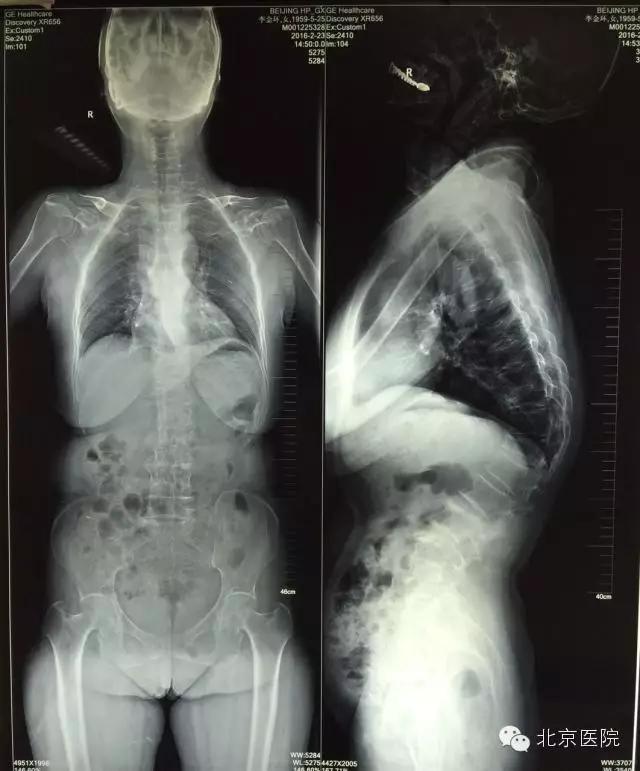

3月中旬,来自河北省大城县的56岁的李女士,十几年前的外伤导致了她胸椎骨折,在当地落后的医疗条件下,采取保守治疗后患者有两节椎体变形,慢慢的使得患者像个80多岁的老年人一样,弯了腰驼了背。多年来腰背痛一直伴随着李女士,并且逐渐加重,导致她日常生活、活动能力都严重受损。她不但不能像正常人一样劳动,还成为了家庭的负担,使得患者整个家庭都陷入了痛苦。后来经人介绍,患者在家属的陪同下来到了北京医院骨科,就诊于孙常太副主任的门诊。经过仔细的查体和评估,诊断为胸腰椎后凸畸形、重度骨质疏松症,孙常太副主任将患者收入院并准备手术治疗。

在完善了术前检查后,经过骨科全科专家会诊、脊柱组组内讨论后,制定了适合该患者的详细手术方案。通过术前测量,该患者的后凸畸形成角角度约60°,由于骨折后楔形变的胸12椎体前缘高度下降太多,导致脊柱后凸的顶点位于胸12椎体,故采取了经胸12椎弓根椎体截骨矫形手术。这种手术通过将变形的椎体截去三角形的一部分,把椎体后缘的高度降低到跟前缘一样,从而把后凸变形的脊柱“掰直”,然后通过椎弓根钉棒系统牢牢地将脊柱固定在符合生理力线的位置上,有效的缓解了胸背部的肌肉张力,从而大大缓解了患者的腰背部疼痛。该手术由孙常太副主任、申剑副主任医师、王强副主任医师等组成的治疗组实施,在手术麻醉科的喻震、郭晓曦等同仁的全力配合下,术中精心操作,小心避开了极易损伤的脊髓圆锥部分,顺利的完成了截骨、矫形、固定等步骤。术后该患者在骨科高凡护士长带领的优秀护理团队的精心照料下,安全康复,术后第6天即下地活动,下肢神经功能完全正常,腰背部疼痛得到了明显地缓解,并于术后第9天顺利出院回家。